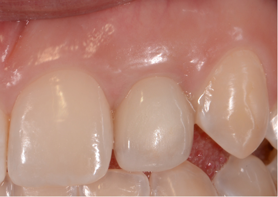

Figure 12 shows the temporary abutment (left panel) after the implant and connective tissue graft were placed, and the patient 2 weeks postoperatively (right panel). Seven years later, the restoration remains sound (Figure 13).

Fig 12. Left panel: temporary abutment in the patient with the congenitally missing tooth No. 10. Right panel: Two weeks postoperatively after the implant and connective tissue graft placement. (Images courtesy of Dr. Keith Progebin.)

Figure 12

Fig 13. Patient with congenitally missing tooth No. 10 at 7 years postoperatively.

Figure 13